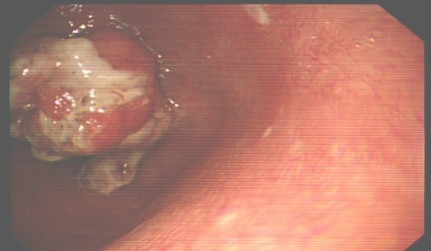

Fémina de 78 años con Anemia Crónica, constipación y enterorragia de 6 meses de evolución, en la hematología presentaba déficit de hierro, hipocromía y microcitosis de la lámina periférica. Se realizó Videocolonoscopia con el diagnóstico de Tumor Maligno Avanzado del Colon, por presentar una lesión infiltrante, extensiva con mucosa friable y rígida a la toma de biopsia, en el ángulo hepático, que impidió avanzar con el equipo. Se recogió muestra para estudio histológico.

La TC Abdominal mostró un engrosamiento tumoral de la pared del colon de 20.3mm a nivel del ángulo hepático con una longitud de 59mm provocando estenosis de la luz a forma de roído de manzana, la cual midió de diámetro máximo 5,7 x 4,5cm, en cortes axiales con alteraciones en la densidad de la grasa peri tumoral dando el aspecto tomográfico de neoplasia de colon derecho a forma estenosante.

No se observó líquido libre en cavidad, ni adenopatías ni masas en otros órganos de la cavidad, correspondiendo a un Estadio I-II, según criterios de estatificación tomográficas antes mencionados. Posteriormente se confirmó el diagnóstico de Adenocarcinoma Bien Diferenciado por estudios histológicos. Se realizó tratamiento quirúrgico con resección del tumor sin evidencias macroscópicas de lesiones secundarias en órganos de la cavidad abdominal. Posteriormente falleció la paciente por complicaciones postquirúrgicas mediatas.